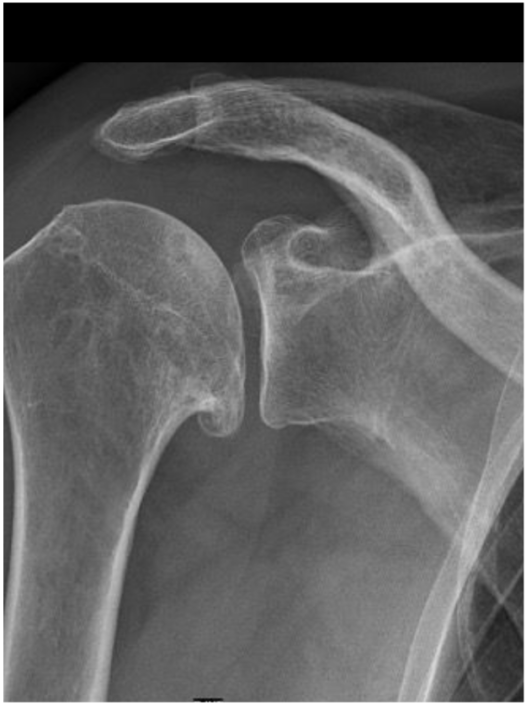

We spreken van slijtage als er sprake is van vermindering van de beweeglijkheid van het gewricht, gecombineerd met afwijkingen op de röntgenfoto. Je kunt ook van slijtage spreken als je dit alleen ziet op de foto, maar bij geen klachten noemen we dit dan ‘passend bij de leeftijd’.

Röntgen bij artrose

Bij pijn en afname van de beweeglijkheid in combinatie met leeftijd kan je denken aan schouderartrose. De diagnose wordt officieel bevestigd met röntgen. Röntgen heeft als nadeel dat het met straling gepaard gaat. Dit wordt zoveel mogelijk vermeden, aangezien dit slecht voor je kan zijn.